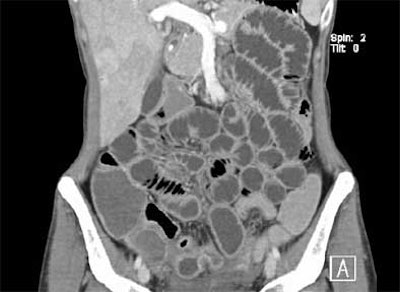

| All images are of a 21-year-old woman who presented with symptoms typical of Crohn's disease: recurrent episodes of hemorrhagic diarrhea, abdominal pain, weight loss, and fever. Endoscopy showed segmental changes in the colon and the terminal ileum; histopathology showed granulomatous mucosal inflammation. In image above, normal enteroclysma CT, coronary reconstruction, shows optimal distension of small-bowel loops. All images courtesy of Dr. Johannes Sailer and Dr. Philipp Peloschek, Department of Radiology, Medical University of Vienna. The group will present its CT enteroclysis results later this month at RSNA scientific presentation presentation No. SSQ06-06). |